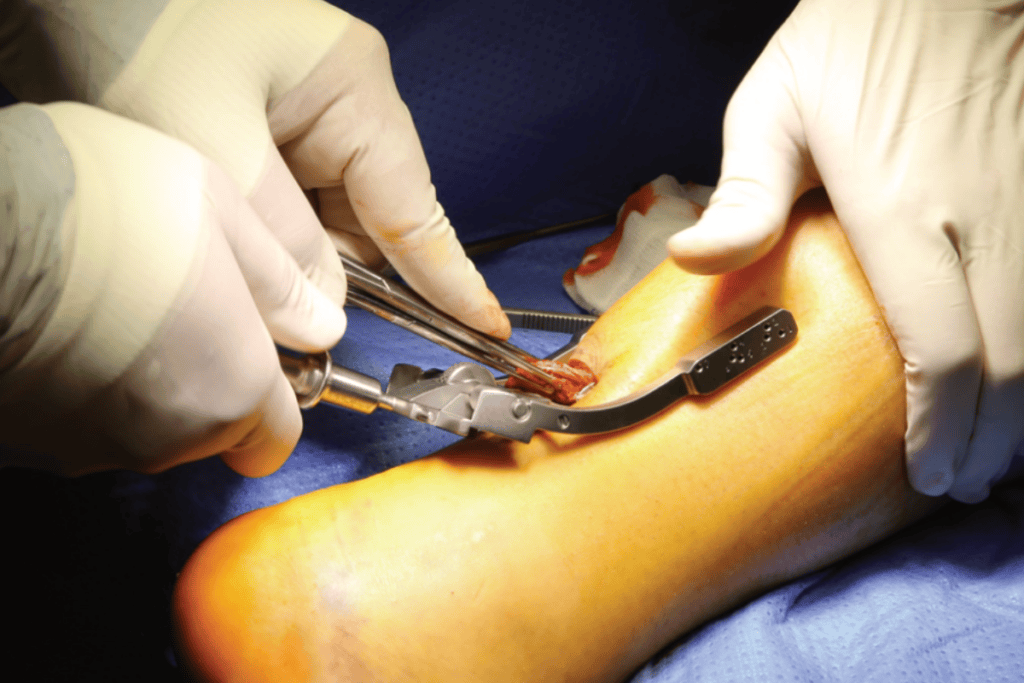

- operacje metodą otwartą – klasyczna rekonstrukcja ścięgna przy pomocy szwów wzmacniających (np. technika Krackowa),

- techniki małoinwazyjne – pozwalają na zszycie ścięgna ze znacznie mniejszych, punktowych nacięć skóry; ryzyka związane z infekcją i gojeniem się ran pooperacyjnych są dużo mniejsze; minusem jest mniejsza kontrola nad układem włókien i ostateczną długością zszytego ścięgna,

- nowoczesne techniki szwu (SpeedBridge, PARS) – minimalizują one ryzyko powikłań i przyspieszają powrót do aktywności.